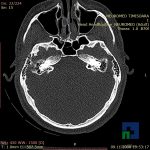

În cazul traumatismelor cranio-cerebrale:

- Evaluarea deplasării liniei mediane

- Evaluarea cisternelor perimezencefalice

- Diagnosticul edemului cerebral, a contuziei cerebrale, a leziunilor axonale difuze edematoase/hemoragice, a dilacerării cerebrale, a hematomului intraparenchimatos posttraumatic, a hematoamelor subdurale/extradurale (acute, subacute, cronice), a hemoragiei intraventriculare, a hemoragiei subarahnoidiene

- Diagnosticul traumatismelor de bază de craniu

- Diagnosticul fistulei LCR

- Diagnosticul herniilor cerebrale